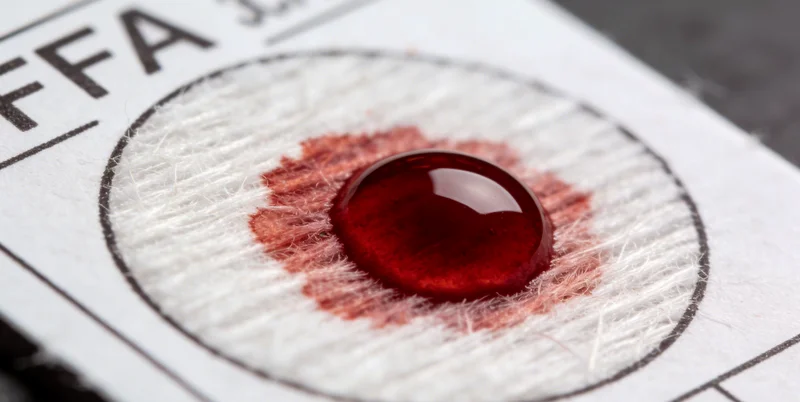

- 样本采集:通常在合作医院的采血点,由护士抽取少量外周血(或用专用的口腔拭子采集口腔黏膜细胞)。这个过程和普通抽血类似,安全无创。样本会放入专用的样本转运箱,由专业的物流冷链配送到实验室。